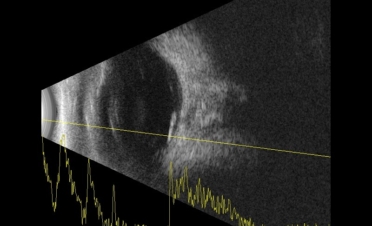

Se le realizó una ecografía y una retinografía para confirmar el diagnóstico.

La ecografía permite observar las estructuras del globo ocular cuando la transparencia de la córnea está comprometida o cuando deseamos observar con detalle los segmentos anterior y posterior del ojo.

En ambas pruebas se observaron imágenes compatibles con un desprendimiento de retina:

Imágenes de la ecografía de Fox, un perro de raza Pomerania con desprendimiento de retina en ambos ojos. Se descartaron otro tipo de lesiones oculares. Foto: IVO. (Clicar la fotografía para ampliar)